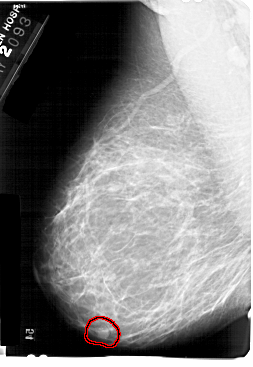

A_1369_1.LEFT_CC

LEFT_CC LINES 5491 PIXELS_PER_LINE 4021 BITS_PER_PIXEL 12 RESOLUTION 43.5 OVERLAY

FILE: A_1369_1.LEFT_CC.OVERLAY

TOTAL_ABNORMALITIES 1

ABNORMALITY 1

LESION_TYPE MASS SHAPE OVAL MARGINS CIRCUMSCRIBED

ASSESSMENT 4

SUBTLETY 5

PATHOLOGY BENIGN

TOTAL_OUTLINES 1

BOUNDARY